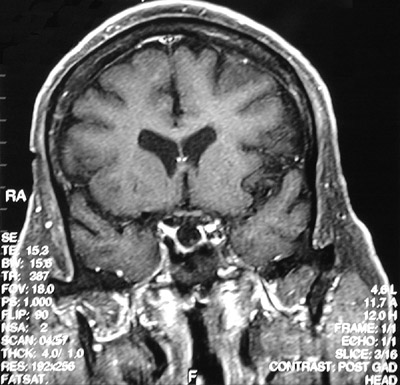

| The T1 weighted MRI scan in sagittal view above demonstrates an empty sella turcica. A T1 weighted post gadolinium coronal view is seen below. Some cases of empty sella syndrome may result from a herniation of the arachnoid through the diaphragma sella to cause pressure atrophy of the pituitary. |